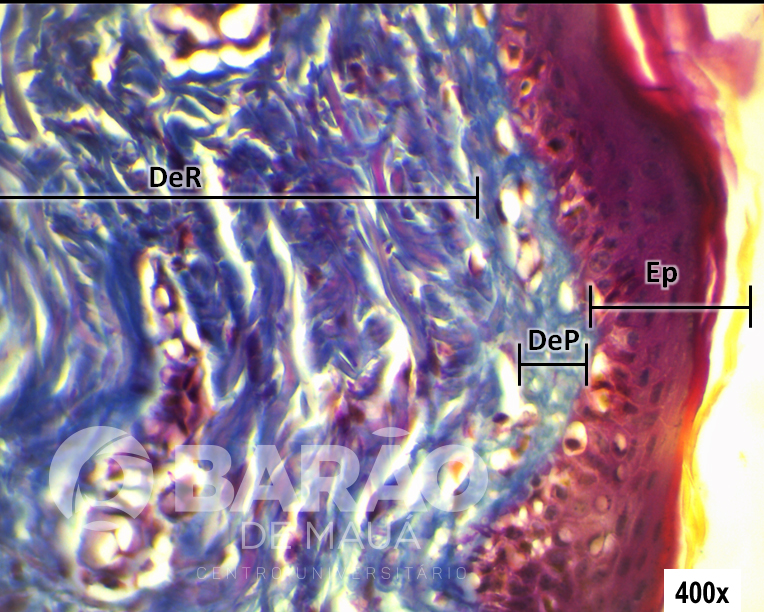

Pele Grossa - Ep = epiderme, DeP = derme papilar (tecido conjuntivo frouxo) e DeR = derme reticular (tecido conjuntivo denso não modelado) - Coloração: H&E

Pele Grossa - Ep = epiderme, DeP = derme papilar (tecido conjuntivo frouxo) e DeR = derme reticular (tecido conjuntivo denso não modelado) - Coloração: H&E.